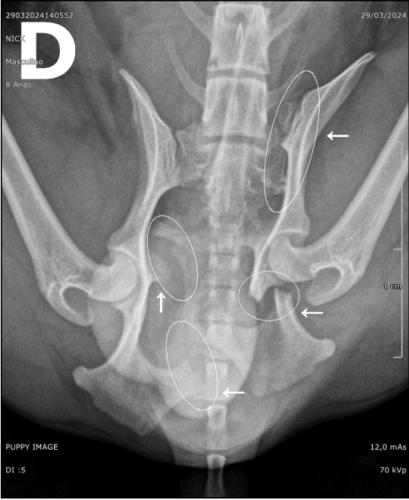

Meu nome é Neto. Criei essa vaquinha para arrecadar R$3.500,00 para ajudar meu tio a realizar a cirurgia do seu cachorrinho que foi atropelado. Após exame radiográfico a impressão diagnóstica do médico veterinário foi: “Disjunção sacroilíaca esquerda associada a múltiplas fraturas pélvicas e em sacro recentes, reduzindo discretamente o canal pélvico, associado a edema de partes moles. ”.

Existe o risco da perda de movimento da perna traseira. E mesmo realizando a cirurgia, ainda há esse risco, podendo haver necessidade do uso de cadeirinha para locomoção.